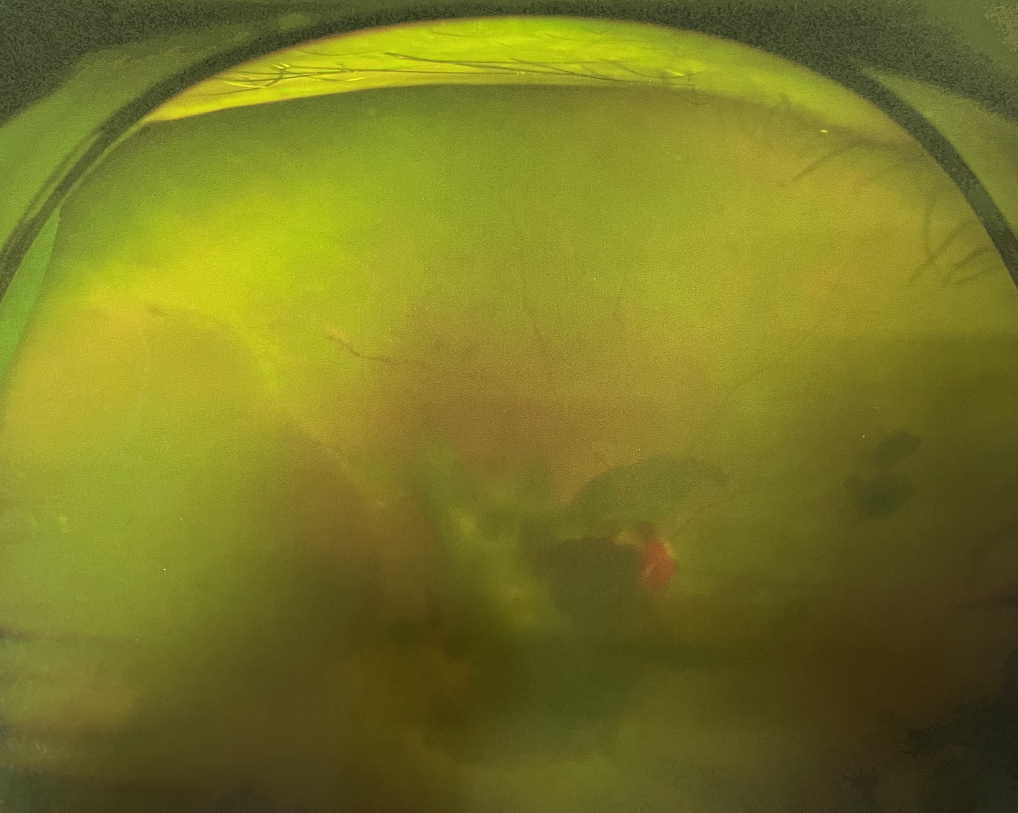

右眼術(shù)前

四十多歲的王女士,患高血壓病及Ⅱ型糖尿病多年,一直靠藥物控制血壓和血糖。去年,王女士右眼看手機(jī)時(shí)感覺視物不清,總感覺眼前有一層霧,視力也逐漸下降,于是來廈門大學(xué)附屬?gòu)B門眼科中心就診。

眼底病??茝埿』⑨t(yī)生檢查后,診斷王女士為“雙眼玻璃體積血、雙眼糖尿病視網(wǎng)膜病變V期”。(V期即5期,纖維增生期,出現(xiàn)纖維膜,可伴視網(wǎng)膜前出血或玻璃體出血。)

張小虎醫(yī)生為王女士進(jìn)行右眼玻璃體腔注藥術(shù),3天后進(jìn)行右眼23G玻璃體切割術(shù)后視力有所提升。

4個(gè)月后王女士來院取硅油,取油后視力恢復(fù)到0.6。“當(dāng)時(shí)來的時(shí)候真的只能看到模糊的影子,特別害怕覺得完了,想說眼睛估計(jì)要瞎了,沒想到手術(shù)后視力竟然提升了,現(xiàn)在也看得比較清楚了。”王女士說到。

張小虎醫(yī)生表示,糖網(wǎng)病進(jìn)展到嚴(yán)重增殖期帶來的視力損傷往往是極其嚴(yán)重的,目前王女士右眼從術(shù)前0.02恢復(fù)到術(shù)后0.6,已屬十分難得。